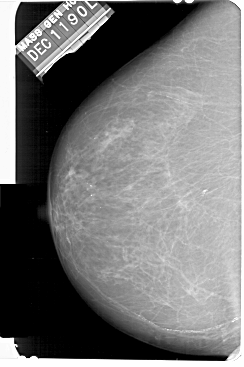

A_1511_1.LEFT_CC

LEFT_CC LINES 5491 PIXELS_PER_LINE 3646 BITS_PER_PIXEL 12 RESOLUTION 43.5 NON_OVERLAY